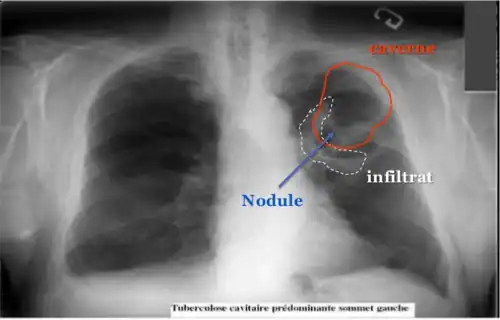

Diagnostic radiologique

La modalité de diagnostic radiologique se révèle très utile et indiquée comme étant un examen de première intention en cas de tuberculose pulmonaire et ostéoarticulaire[78]. Cela est justifié par les images radiologiques plus ou moins spécifiques à la tuberculose. La littérature rapporte que la spécificité varie de 27 à 81 % selon l’étude. Les imageries idéales et révélatrices de la tuberculose répondent à certains attributs dont le premier est lié au siège. En raison de l’affinité que les BK ont envers les régions aérées, la lésion radiologique est souvent observée dans les parties hautes des poumons. Néanmoins, l’image radiographique peut contenir différentes formes :

- infiltrat : traduisant des lésions débutantes de l’infection via une opacité peu dense, hétérogène et étendue ;

- nodule : granulome de taille variable, isolé ou groupé ;

- tuberculome : nodule isolé pseudotumoral ;

- caverne : excavation par perte de substance au sein d’un infiltrat, aux parois épaisses.

Les cavernes sont une complication fréquente de la tuberculose pulmonaire[55]. On appelle caverne une cavité creusée au sein du parenchyme pulmonaire[56]. Les bacilles tuberculeux se développent initialement dans le poumon sous forme de nodules, appelés granulomes, qui sont peu à peu entourés de lymphocytes et de macrophages destinés à contenir l'infection[55]. Un granulome peut évoluer soit vers la disparition sans cicatrice, soit vers la caverne, sans que les mécanismes sous-jacents soient compris en totalité[56]. Les vestiges de macrophages détruits occupent le centre du granulome et forment la majeure partie de la nécrose caséeuse[56]. Chez certains patients, cette nécrose caséeuse se liquéfie et devient un milieu de culture adapté aux bacilles, qui prolifèrent. Des enzymes protéolytiques érodent alors la capsule fibreuse située en périphérie du granulome, et son centre liquide peut alors se vider peu à peu[56]. Lorsqu'une caverne tuberculeuse arrive en communication avec l'arbre bronchique, la dissémination des bacilles dans l'air expiré augmente la contagiosité[55],[57]. Par ailleurs, la quantité importante de bacilles contenus dans les cavernes favorise le développement de résistances aux anti-tuberculeux[57].